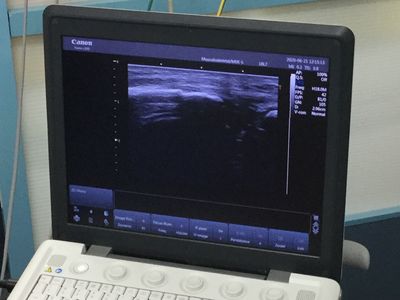

エコーで確認したところはっきりとした骨折の線が見られました。病院を紹介しレントゲンを撮ってもらうようお願いしました。

下にはエコー像と手技を行なっている時の写真です。